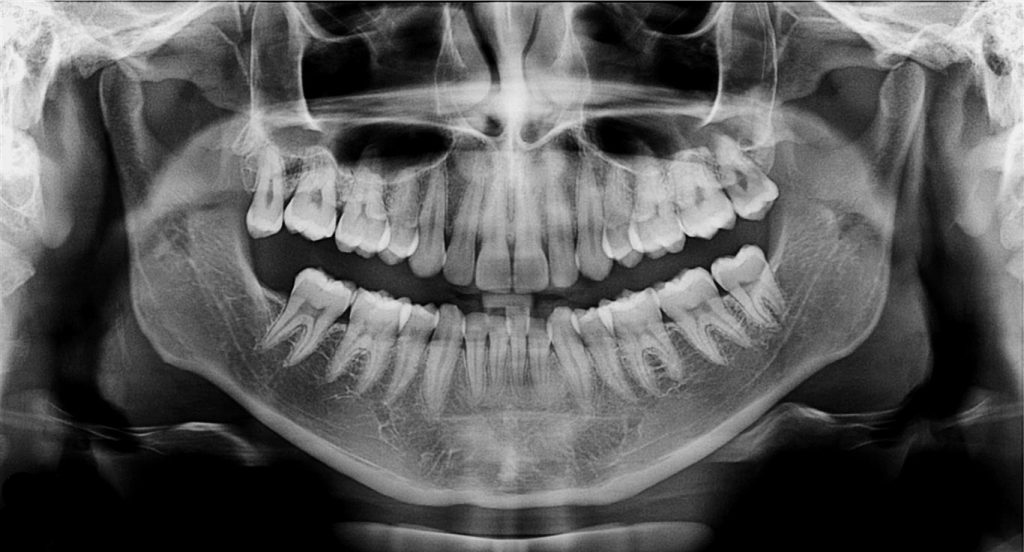

Radiografia panoramica

Es una técnica radiológica que permite dar una amplia visión del estado de los maxilares y piezas dentarias mediante una radiografía panorámica de baja radiación , se realiza con un equipo adecuado para este propósito y nos ayuda a diagnosticar problemas con una visión general, esta puede realizarse rápidamente y el mismo dia de la consulta, en caso de encontrarse alguna alteración en las estructuras se podra solicitar una tomografía CONE BEAM, tambien disponible para nuestros pacientes